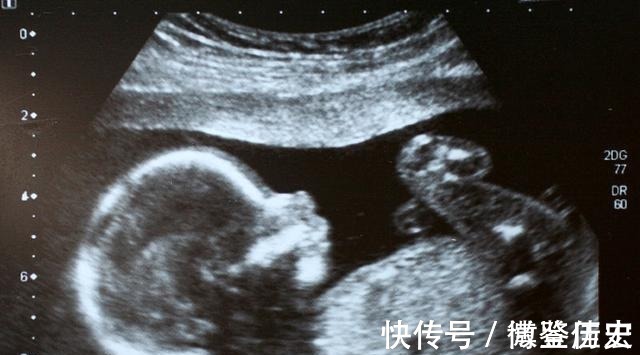

据统计,我国先天残疾儿童总数高达80~120万,占我国出生人口总数的4%~6%。严重的畸形可导致胎儿/新生儿死亡或严重残疾。当宝宝在肚子里慢慢的长大,父母慢慢的感受到胎动,对宝宝的爱与日俱增,对宝宝的期待也愈加强烈。但当孕期查出畸形,满怀期待的我们,又该如何抉择呢?

宝宝畸形的临床表现有哪些呢?1、程度较轻,对孩子将来影响较为轻微常见的轻微畸形的一般为:六指、小耳畸形、缺手、指唇腭裂、膈疝、脐疝、室间隔缺损等。这些畸形在孩子出生后面,都可以用一定的医学手段来矫正,不矫正对孩子生活影响也不是太大。